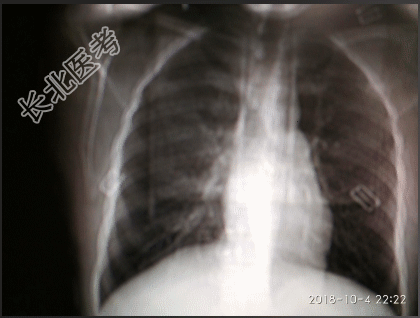

- [材料题] 【一般资料】男性,63岁,农民【主诉】间断咳嗽、气喘6年,加重1个月入院。【现病史】于入院前6年,无明诱因出现咳嗽、气喘,咳白色粘痰,呈阵发性,每年5-6月份发作频繁,不伴发热,无胸痛、胸闷,无头痛、头晕,无恶心、呕吐,曾在当地诊所就诊,给以对症治疗(具体名量不详),症状好转。近1个月来,患者上述症状加重,曾在当地诊所就诊,给予静点药物(具体名量不详)治疗,效果不佳,今日为进一步明确诊治而来我院,查胸片示:支气管炎。遂以“支气管哮喘继发感染”收入院。自发病以来,精神、饮食及睡眠均欠佳,二便正常。【既往史】既往无高血压、冠心病、糖尿病病史,无肝炎、结核等传染病病史,无外伤、手术及输血史,否认药物及其它过敏史。预防接种史不详。【查体】T:36.5℃,P:102次/分,R:20次/分,BP:166/97mmHg。神清,端坐位,全身皮肤黏膜未见黄染,周身浅表淋巴结未触及肿大。口唇发绀,咽无充血,颈软,甲状腺不大。两肺听诊呼吸音粗糙,两肺闻及哮鸣音。心界无扩大,心率105次/分,节律规整,心音低钝,各瓣膜听诊区未闻及病理性杂音。腹软,无压痛、反跳痛,触无包块,肝脾肋下未触及,叩鼓音,移动性浊音阴性,听诊肠鸣音正常存在。双肾区无叩痛,双下肢无水肿。四肢肌力、肌张力正常,生理反射存在,病理反射未引出。【辅助检查】胸片示:支气管炎。